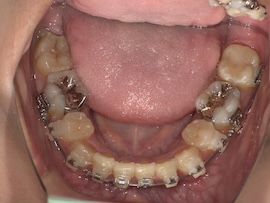

そこから1ヶ月後、

再度レントゲンにて左上親知らずの状態を確認したところ手前の歯に引っかかっていそうだったので、親知らずにもブラケットをつけてバネで押しながら引っ張るように調整してもらいました。